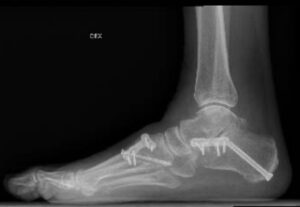

Kuudennen viikon aluksi otettiin uudet röntgen-kuvat – viikon verran etuajassa, koska ortopedi halusi tutkia jatkuneen kipuilun syytä. Oli hiukan pelottavaa hypätä terveellä jalalla kuvaustasanteelle siten, että leikattu jalka oli ilman suojaa, paljaana. Tähän asti jalka oli koko ajan ollut kipsissä tai Walker-saappaassa. Ilman tukea hyppääminen vaati rohkeutta tällaiselta 63-vuotiaalta mummolta. Kuvien mukaan leikkaus oli onnistunut